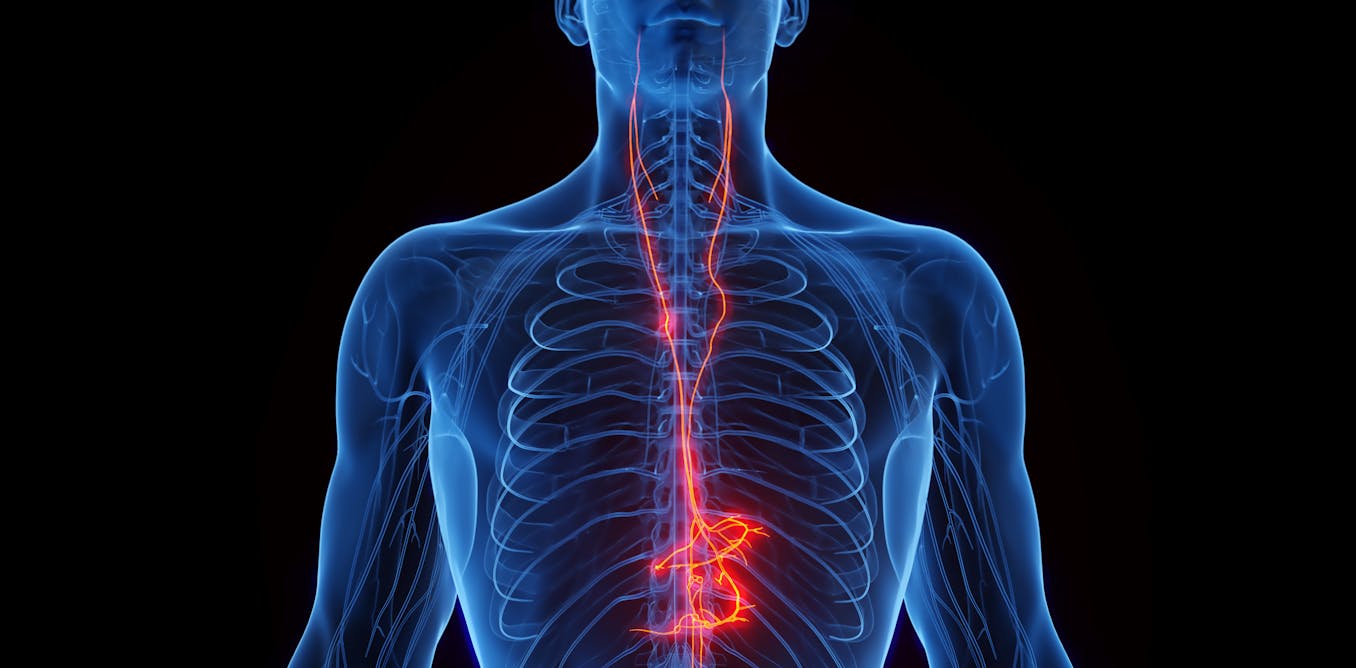

The vagus nerve carries information between the brain and organs in the chest and abdomen, such as the heart and intestines, helping the brain monitor and regulate many of the body’s essential organs. It is responsible for sending rest and digest messages throughout the brain and body, stimulating digestion and promoting cellular repair.

Vagus nerve stimulation for epilepsy and depression generally involves implanting an electrical stimulator in the left side of a patient’s chest, where the vagus nerve passes. Noninvasive devices for treating headaches deliver gentle pulses of electricity to certain places on the neck or ear where the vagus nerve is very close to the surface of the skin.